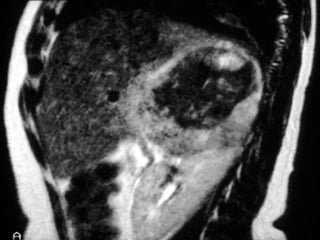

Hemorragia da supra renal